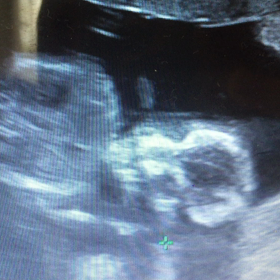

• 12w5d*まさかの性別判明?!とつわりの画像

12w5d*まさかの性別判明?!とつわり